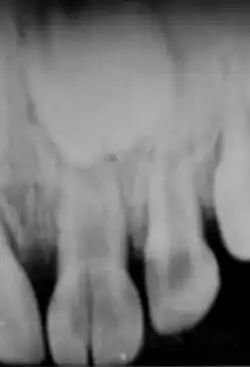

Messaufnahme – während der Wurzelbehandlung eines frakturierten Frontzahnes (11)

Röntgenkontrollaufnahme der fertigen Wurzelfüllung